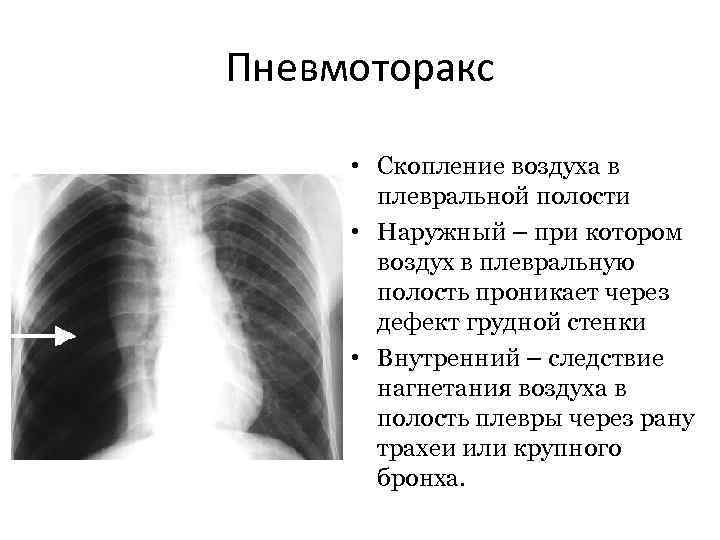

Схемы дыхания: Пневмоторакс на изображениях